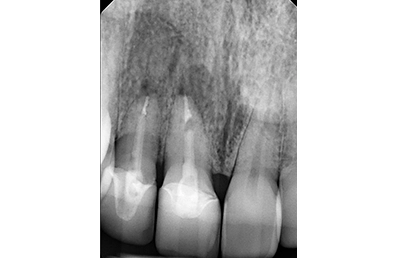

Initial periapical radiograph

Chief Complaint: The patient presented with an upper right lateral incisor exhibiting mobility. Further examination revealed a history of endodontic treatment combined with root fracture.

Intraoral Assessment: Porcelain crowns were present on the upper right lateral and central incisors. The upper right central incisor displayed a root canal treatment, a periapical lesion, and a root fracture accompanied by discolored and inflamed gingiva. The lateral incisor had a periapical lesion deemed untreatable by the endodontist. The gingival papilla was receding between these teeth, manifesting as a visible black triangle.